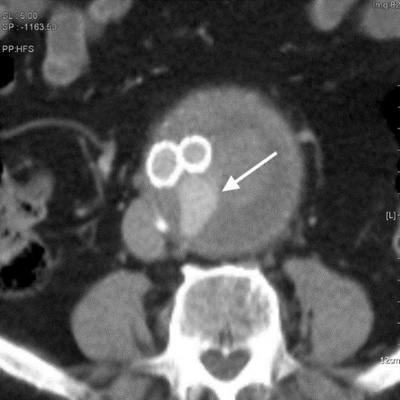

Die Mehrzahl der Bauchaortenaneurysmen wird mittlerweile endovaskulär mittels EVAR behandelt. Ein Nachteil dieser ansonsten eleganten minimalinvasiven Methode ist jedoch das Auftreten einer sog. Endoleckage, d.h. eine persistierende Durchblutung des Aneurysmasacks, welches potenziell die Gefahr einer Zunahme des Aneurysmadurchmessers und somit der Aneurysmaruptur birgt. Aktuell werden insgesamt 5 verschiedene Endoleak-Typen unterschieden, die mittels CT-Angiographie oder auch Kontrastmittel-gestützter Sonographie erkannt und unterteilt werden können. Deshalb ist eine bildgebende Nachkontrolle nach Behandlung eines Bauchaortenaneurysmas mittels EVAR unbedingt erforderlich. Je nach Typ der Endoleckage ergeben sich unterschiedliche therapeutische Konsequenzen, welche nahezu ausnahmslos minimalinvasiv interventionell angegangen werden können.

CT-Angiographie nach EVAR zeigt eine residuelle Durchblutung des Aneurysmasacks (Endoleckage).